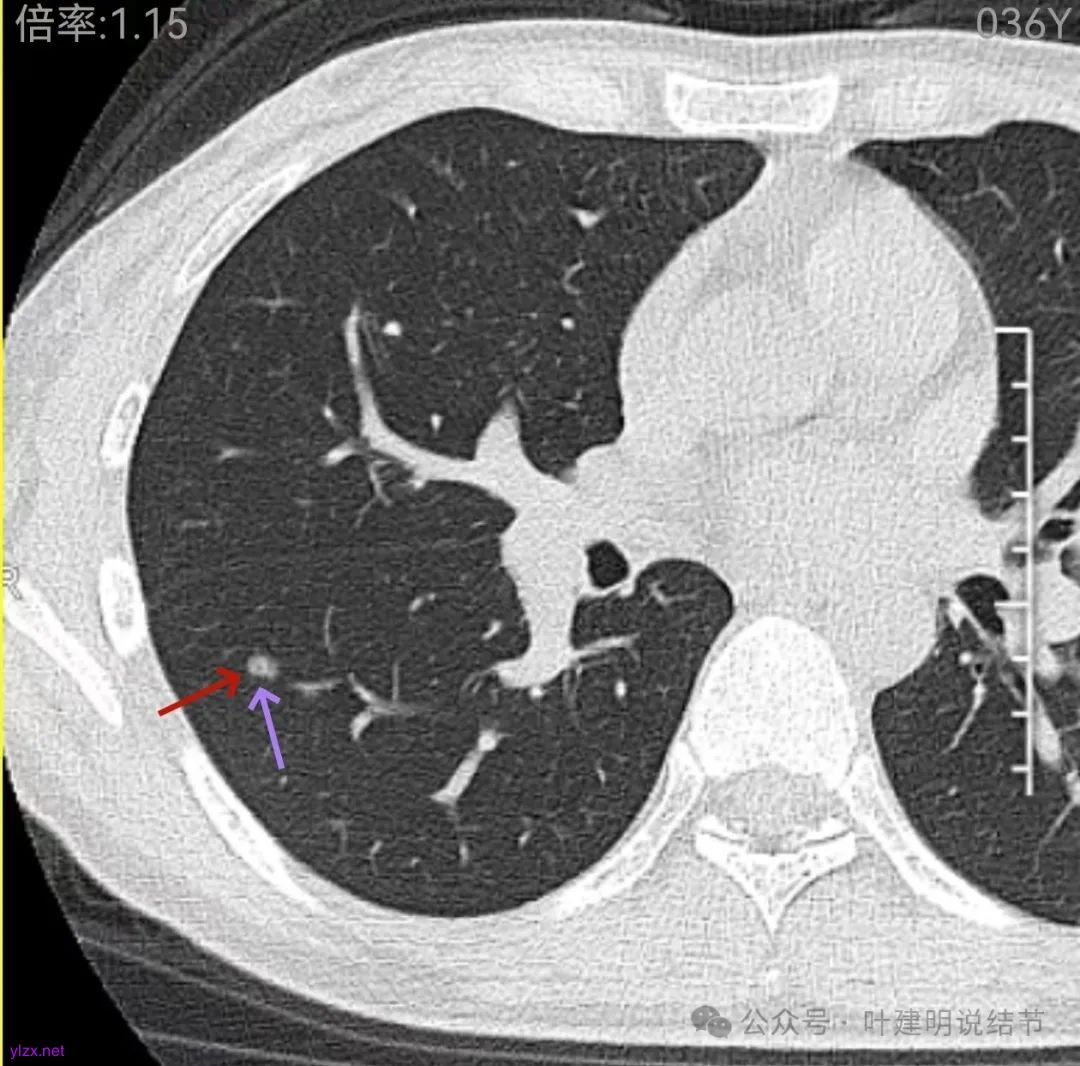

这层面看,密度不纯,部分区域的边缘有细毛刺征。但感觉与前一层面的结节形态不似延续过来的。

边缘区密度也略显高,圆形的样子。

上图层面已经像混合密度了,表面毛糙不光滑,灶内密度不均,也有小空泡征的样子。

感觉这处(在上截图结节的下面点,邻近层面)不像前面病灶的延伸,否则这密度的变化有点突兀呀。